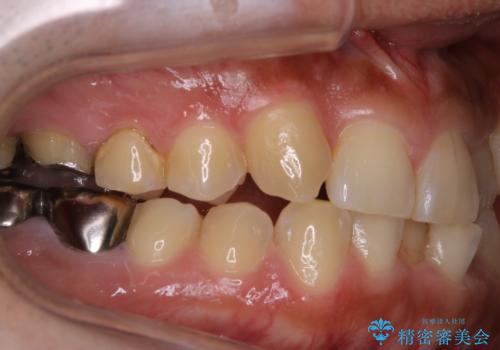

前歯メインにステインの付着が見られ、コース内容を相談した結果PMTC(保険外治療)の30分コースを行いました。

- 矯正治療を考えているため、まずはクリーニングを行いたいとのことで来院されました。PMTC30分コースを行いました。